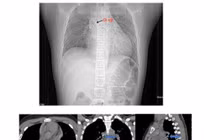

Bệnh nhân được chỉ định chụp CT-scan lồng ngực. Kết quả cho thấy một dị vật cản quang nằm trong lòng phế quản gốc trái – vị trí cực kỳ nguy hiểm vì chỉ cần thêm một chút di chuyển, mảnh xương có thể đâm thủng phế quản, gây biến chứng nặng.

Kết quả, mảnh xương cá hình đa giác, kích thước khoảng 8x16mm, có cạnh sắc bén đã được lấy ra an toàn. Sau thủ thuật, bệnh nhân được theo dõi và điều trị nội khoa ổn định, hết ho – không còn khạc máu và xuất viện sau 1 ngày.